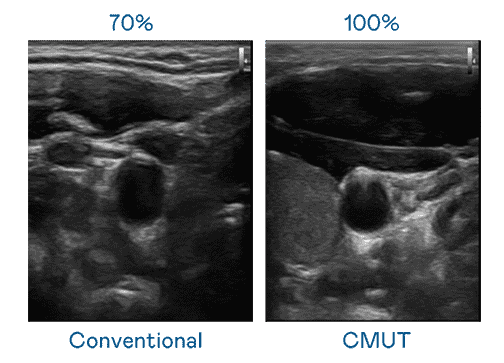

CMUT 技术是一种用电容式微机电元件来产生超音波讯号的技术。。。与传统 PZT 压电式技术相比,,CMUT 频宽增加 30%,,更宽频的超音波讯号让影像解析度大幅提升,,,是实现高影像品质医疗超音波扫描、、、促进精准医疗发展的关键技术。。。。

大频宽带来超清晰影像

超音波影像的解析度高低,,首先取决于探头能发出的讯号频宽。。william威廉中文官网 CMUT 可提供高清晰的超音波讯号,,,提供高频宽、、、、高灵敏度、、影像纹理细节更高的超音波影像,,协助医护人员缩短影像判读时间及利用精准的医疗影像进行诊断。。。。